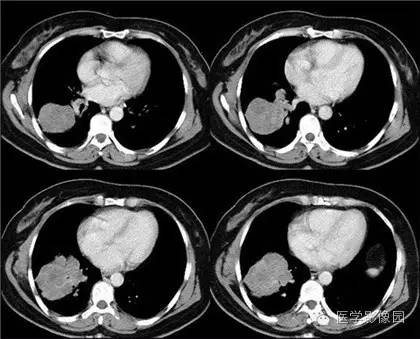

肺纤维肉瘤1例CT影像表现

临床资料:年轻女性,以胸闷、胸痛不适就诊。

影像学表现:右肺下叶见浅分叶肿块,直径大于3厘米,内部密度不均,周围有裂隙,增强后有强化。 医学百科网 | YxBaike.Com

结果:肺纤维肉瘤 医学百科网 | YxBaike.Com

肺肉瘤在影像上常表现为较大孤立肿块,边缘一般比较清楚,较少有毛刺,可有轻度分叶表现。较大的肿块内密度多不均匀,多为肿瘤坏死所致,也可见有肿瘤内部出血的表现,钙化极少见。增强扫描肿块多呈不均匀强化。一般如果不经任何治疗病程进展较快,可很快合并胸腔积液。纵隔淋巴结在病程发展早期可不明显,有少数病例可始终不出现肿大淋巴结。 医学百科网 | YxBaike.Com